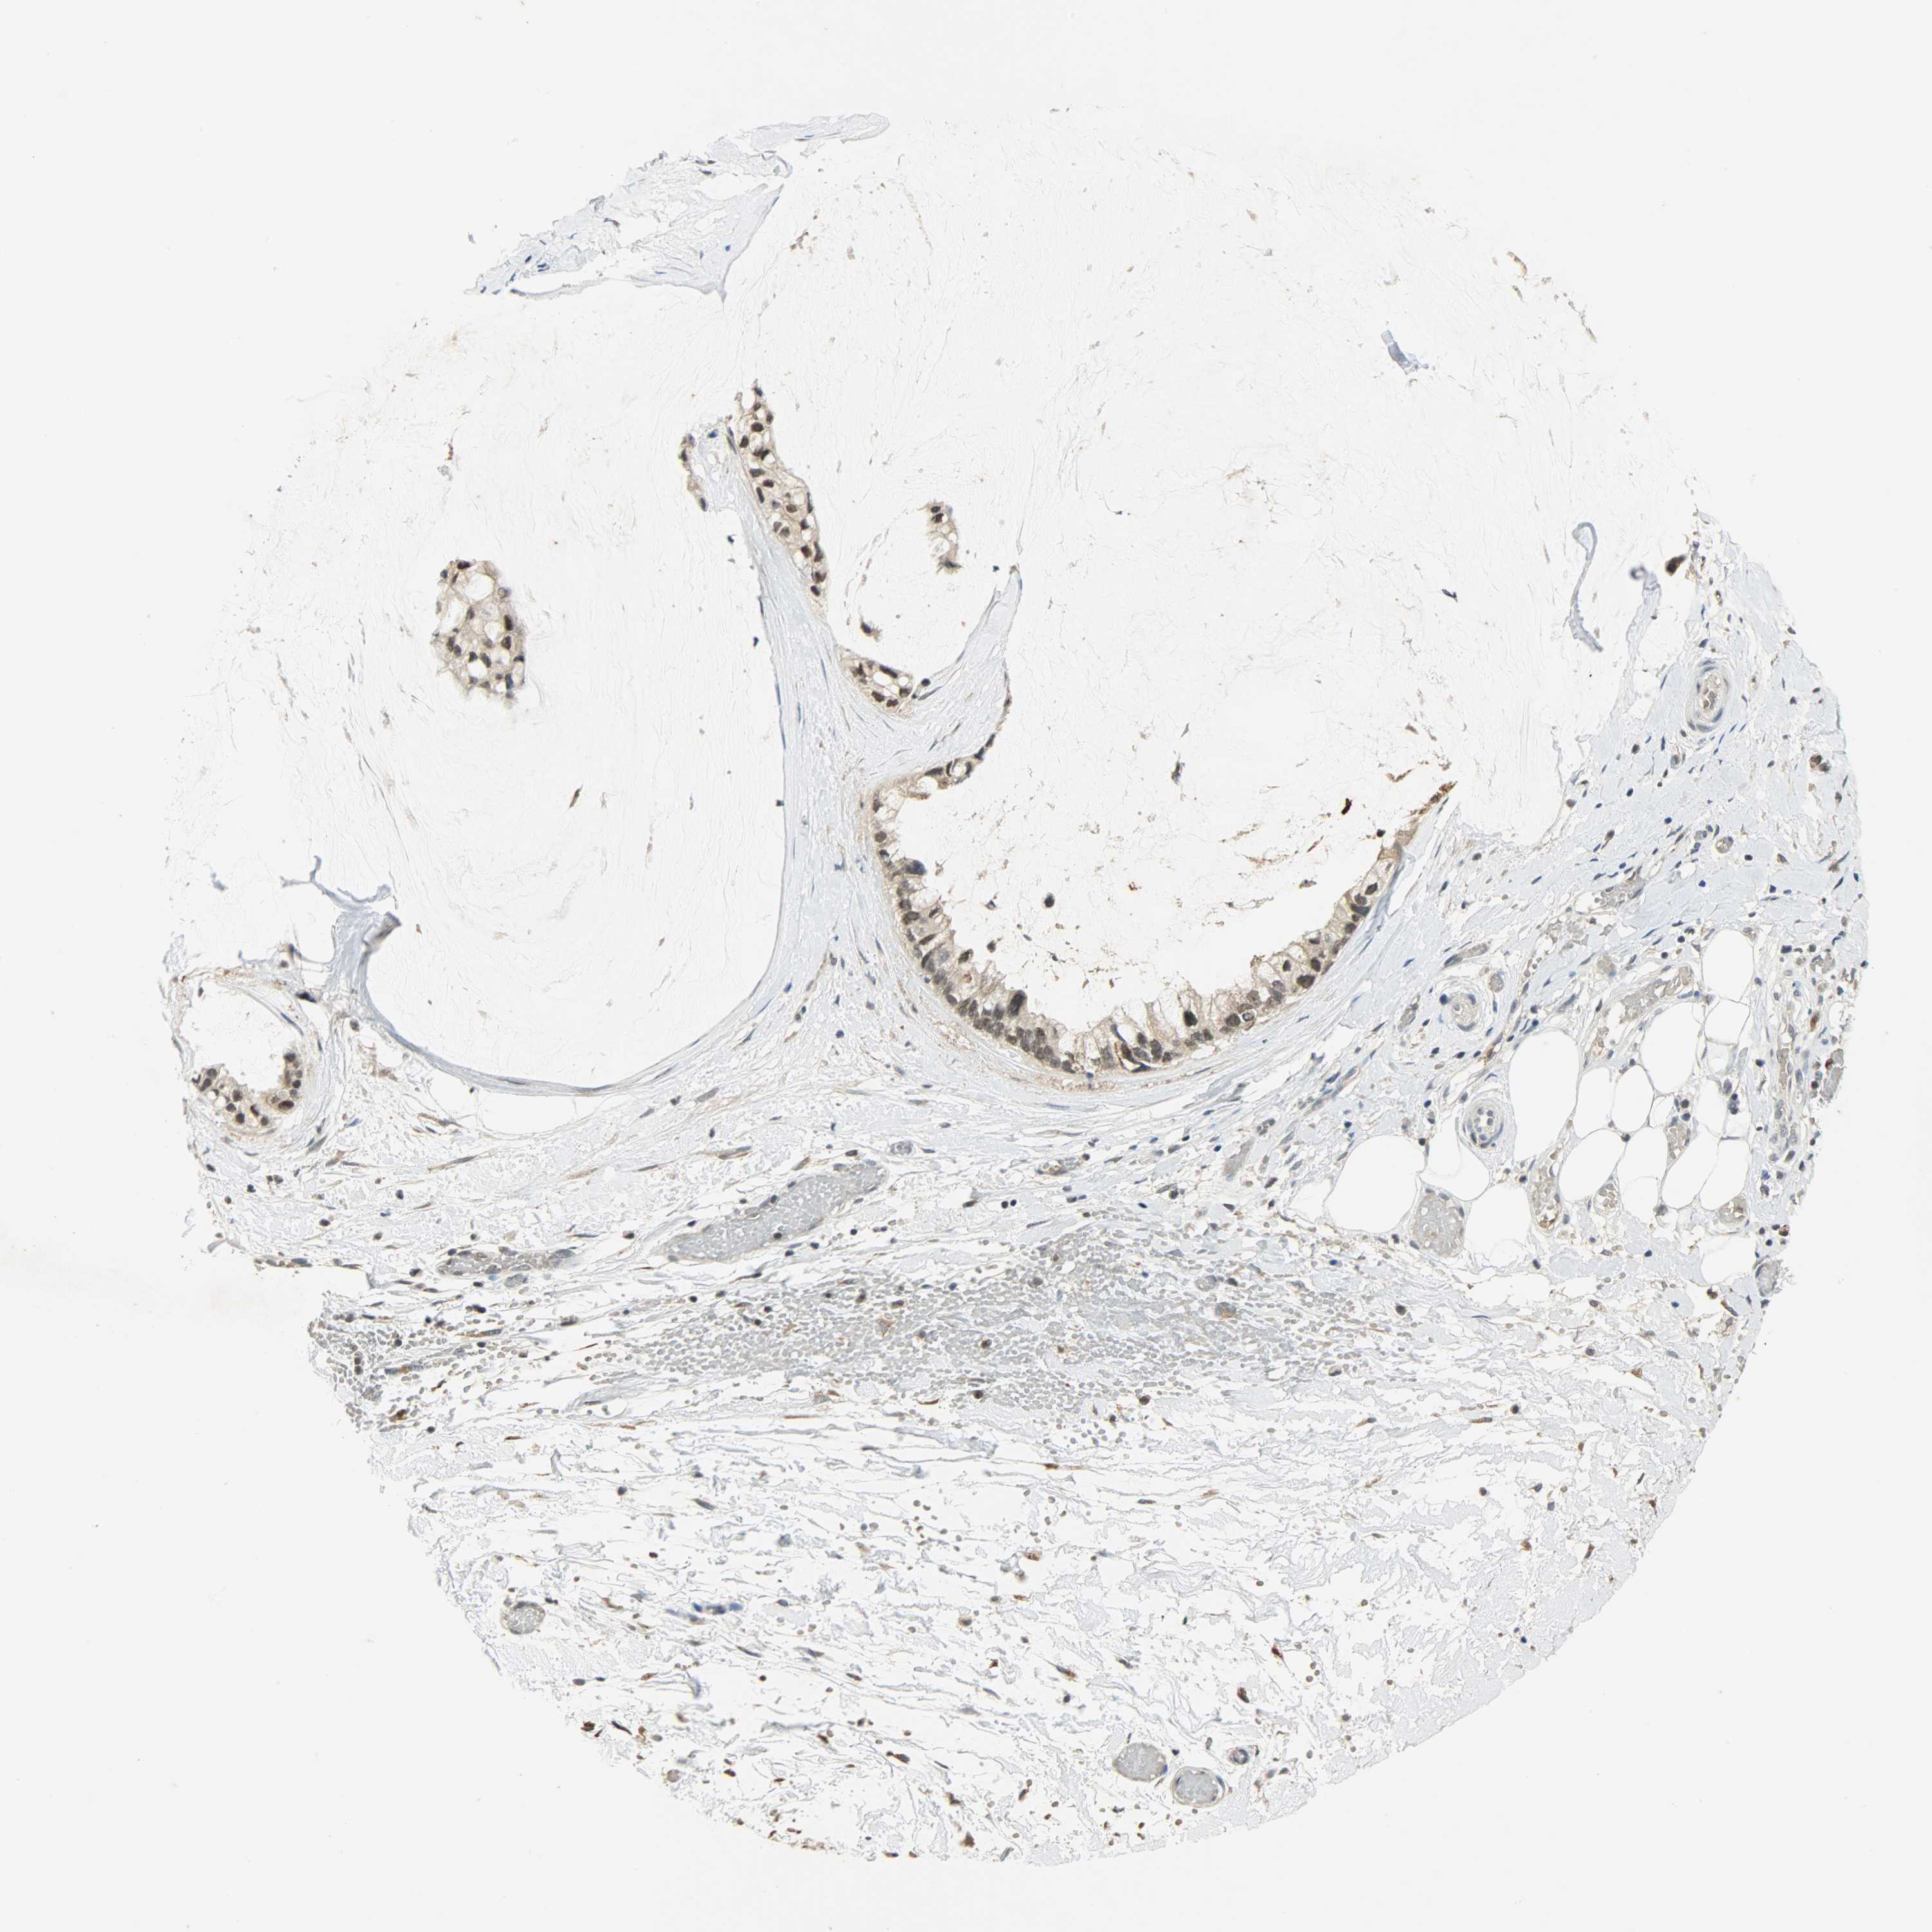

OVARIAN CANCER - Protein expressioni

A mouse-over function shows sample information and annotation data. Click on an image to view it in a full screen mode. Samples can be filtered based on level of antibody staining by selecting one or several of the following categories: high, medium, low and not detected. The assay and annotation is described here.

Note that samples used for immunohistochemistry by the Human Protein Atlas do not correspond to samples in the TCGA dataset.

Antibody stainingi

Antibody staining in the annotated cell types in the current human tissue is reported as not detected, low, medium, or high, based on conventional immunohistochemistry profiling in selected tissues. This score is based on the combination of the staining intensity and fraction of stained cells.

Each image is clickable and will lead to virtual microscopy that enables deeper exploration of all samples and also displays staining intensity scores, fraction scores and subcellular localization as well as patient and tissue information for each sample.

Antibody CAB005227

Cystadenocarcinoma, mucinous, NOS